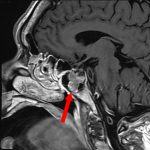

582

'24年10月

50代

頭蓋咽頭腫

頭蓋内腫瘍摘出術

No.’24_84 手術前1

No.’24_84 手術前2

No.’24_84 摘出 前

No.’24_84  摘出 中

No.’24_84 摘出 後